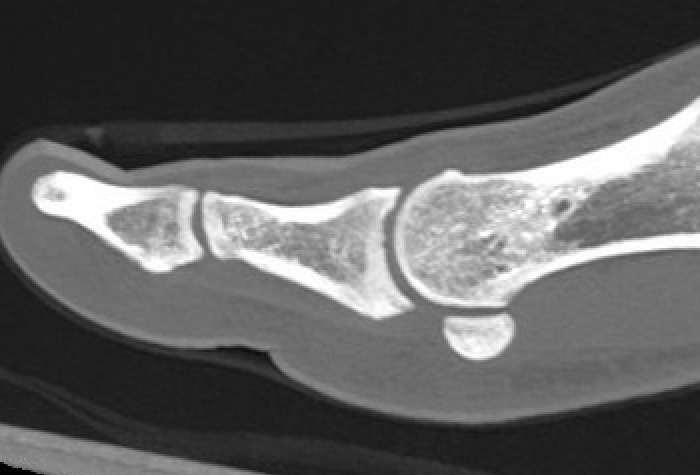

MRI

Sagittal images

Distal avulsion of plantar plate (circle). Star - plantar plate. Arrows - flexor tendon

Complete plantar plate avulsion